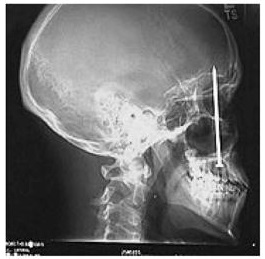

In contrast there have been many accounts of patients sustaining serious injuries that would be expected to be extremely painful. A report in the USA described a construction worker who had unknowingly shot himself in the head with a nail gun and who was unaware of the injury. He perceived a toothache and went to a dentist 6 days later and low and behold a nail was found in his head!! In his head! The patient apparently was completely unaware of the injury and attributed the sensation to more familiar sources, toothache (reference).